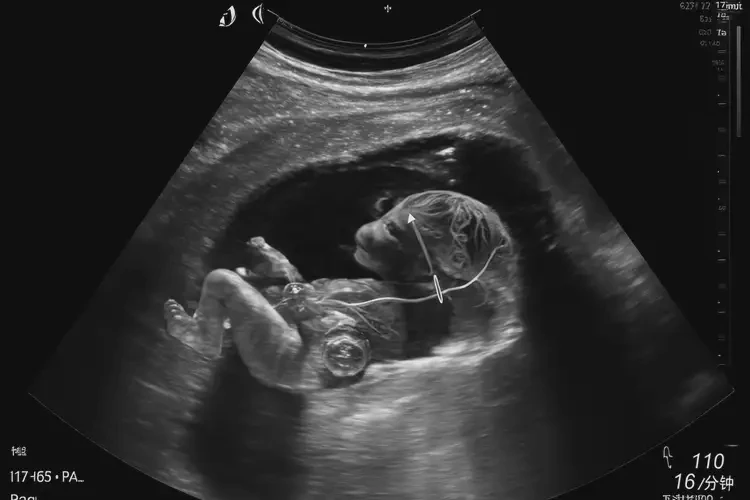

懷孕第17周胎心率85寶寶還能要嗎(圖1)

2. 胎兒超聲檢查

• 胎兒超聲檢查可以評(píng)估胎兒的發(fā)育情況、心臟功能以及是否存在其他結(jié)構(gòu)異常。

• 超聲檢查還可以觀察胎盤(pán)和臍帶的情況,以排除缺氧的可能性。